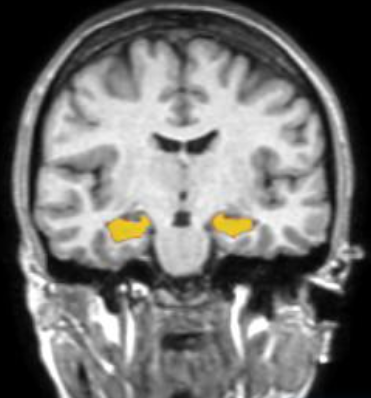

海馬とは?

海馬は、記憶をつかさどる脳の部位です。

記憶力や判断力等の低下は、海馬の萎縮として先に現れることが分かっています。加齢に加え、睡眠不足や運動不足など、生活習慣の乱れがその一因とされています。

しかし、6か月以上の運動をすることによって、海馬で「神経新生」が起こり、体積が増える可能性も示されています。

▲黄色い部分が海馬